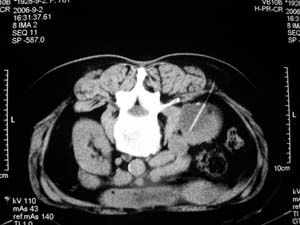

我们主要在ct引导下进行各种囊肿的穿刺引流,对于肾囊肿治疗的较多.穿刺成功后尽量抽尽囊液并且记录数量,抽尽后注入造影剂看看是否与尿路相通,然后用1/4的比例注入无水酒精进行硬化.跟踪观察治愈率达98%以上.